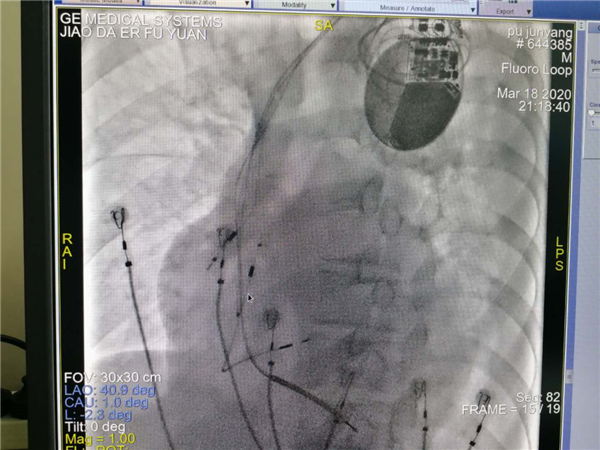

团队术前缜密讨论,充分考虑多个结局,多种策略。手术由郑强荪主任,韩振华副主任,薛嘉虹副教授,王新宏副教授及导管室护士王军、杨宏斌共同完成。团队先为患者行左心室电极植入冠状静脉窦的经典CRTD,但患者冠状静脉窦分支条件较差,左侧后支迂曲盘旋,给操作带来极大的困难,经多次尝试左室电极仍不能植入成功,郑强荪主任、韩振华副主任带领的团队迅速改变策略,与时俱进,决定行左束支区域起搏。另外患者在拔除原右室电极时又因电极与上腔静脉入口处粘连拔除困难,再次为手术带来障碍,最终经团队6小时的不懈努力,手术顺利完成。术后心电图QRS波群由原来的210ms缩窄为160ms,患者心功能明显改善。

术后起搏器留影